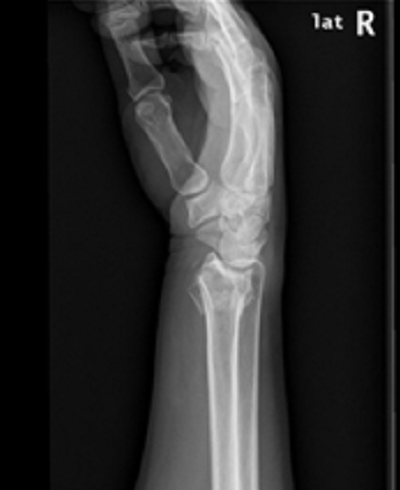

病例一:

诊断:桡骨极远端骨折。

治疗:内固定加外固定治疗。